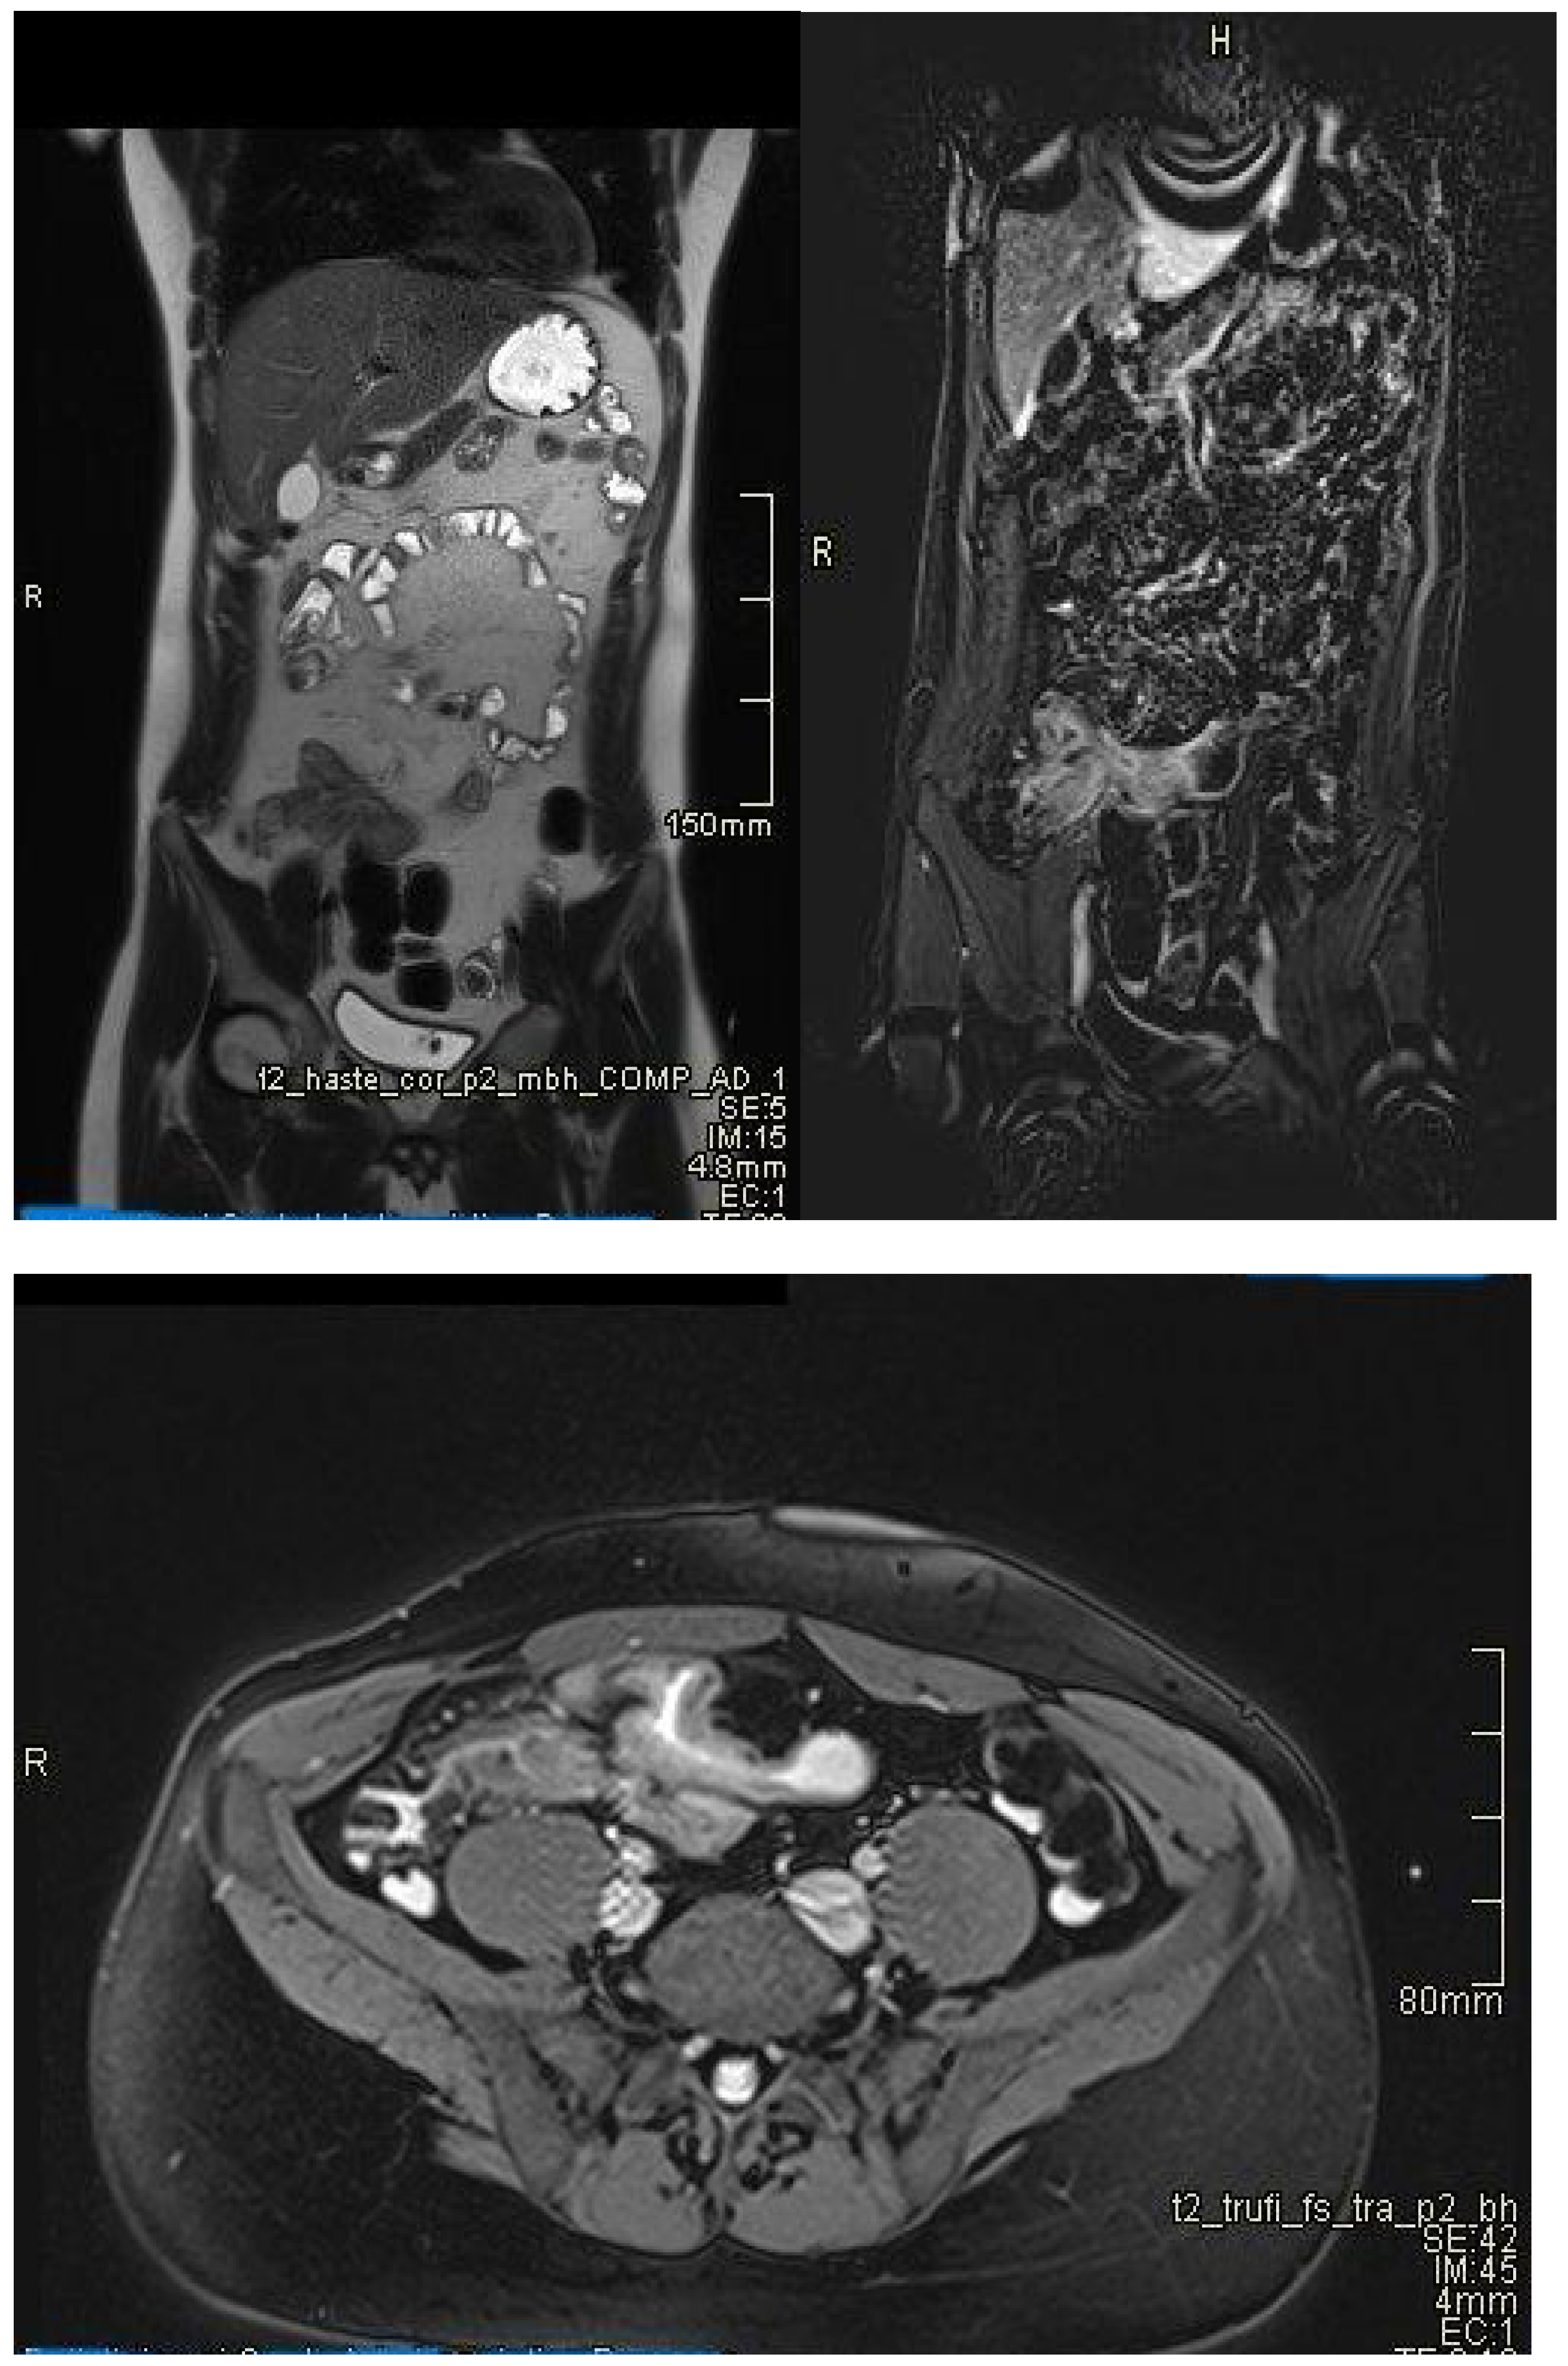

- Magnetic Resonance Enterography (MRE) is essential in the evaluation of inflammatory bowel disease, providing simultaneously detailed images of the intestinal wall and adjacent structures and inflammatory lesions [22], differentiating inflammation from fibrosis in both the small and large intestine submucosa and the perineal area [34,35]. MRE also has high accuracy in staging small bowel inflammatory bowel disease [29], in monitoring treatment response and relapse [22], and in detecting and classifying isolated forms of colonic involvement [36]. This imaging modality is preferred in complex cases with evidence of penetrating, fistulizing, and stenosing lesions [22], as well as in fistulas and perianal sepsis [13]. Fat smudging, fecal sign, fluid level, gaseous distension, comb sign (related vascular congestion), and lymphadenopathy are the elements mainly visualized/detected by MRE [2]. Another advantage—perhaps the most important—is that MRE is the safest and most cost-effective cross-sectional imaging method that can be used to evaluate the activity of Crohn’s disease and ulcerative colitis in both adults and young people [37], without the use of ionizing radiation [2]. Taylor et al. have shown that MRE has a sensitivity of 97% for detecting inflammatory bowel diseases, over 90% for fibro-inflammatory strictures, and specificity of over 95% [29].

- Stenosis

- May be inflammatory (with edema and entrapment) or fibrotic (without inflammatory signs) (Figure 7).

4.1. Differentiating Between Active Inflammation and Fibrosis